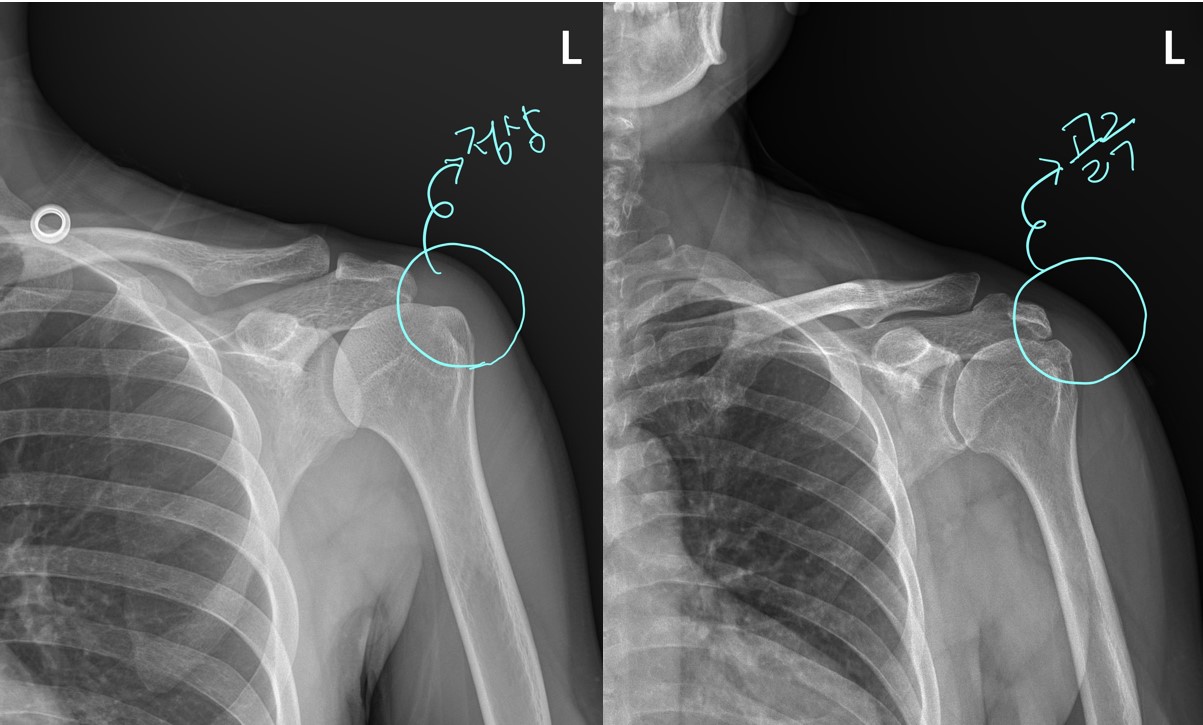

우선 x-ray를 좀 살펴보면..... 이것만 봐도 어깨 상태가 심상치 않음을 느낍니다. 일반적으로 정상적인 X-ray는 위팔뼈의 라인이 둥글둥글하게 부드럽게 넘어가야 하는데 이 환자분의 위팔뼈 부분은 울퉁불퉁하고 뾰족뾰족한 부분이 보입니다.

(당산 당산역 당산동 여의도 합정 목동 영등포 영등포구청 선유도 양평동 국회의사당 정형외과 야간진료 도수치료 통증의학과 박상준의원)

이걸 '골극'이라고 하는데요... 뼈의 특정 부위에 염증이 반복되거나 그 부위에 뭔가 자극이 되면 뼈가 자라는 것을 말합니다.

아프고 불편한지가 수년이 되었는데 x-ray 상에서 이렇게 골극이 보인다는 것은 뭔가 문제가 상당히 있을것을 추측할 수 있습니다.